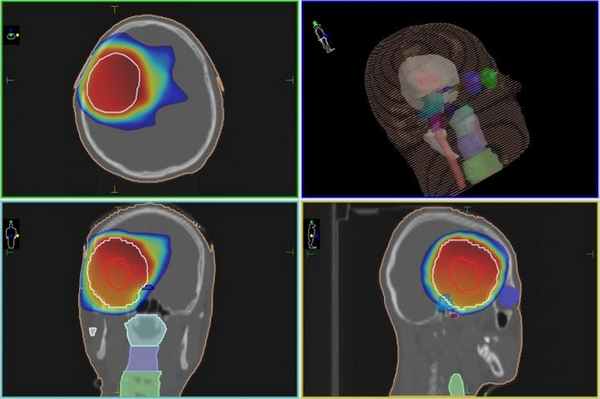

Радиохиругическое лечение глиомы на Киберноже, независимо от типа опухоли, который более точно можно будет определить во время биопсии (если есть возможность ее провести), проводится по одинаковому алгоритму. Сначала с помощью данных КТ- и МРТ-исследований будет сформирована пространственная модель расположения опухоли и соседствующих с ней здоровый участков мозга. Затем в планировочной системе лучевой терапевт задает требуемую дозу, которую КиберНож должен сформировать в области, в границах которой находится глиома.

Также задается минимальная доза в тех зонах, которым любое облучение противопоказано (например, ствол головного мозга). После этого мощная компьютерная система строит план лечения с тем, чтобы из множества тонких одиночных пучков излучения сформировать в опухолевой зоне равномерную зону требуемой дозы излучения. Далее роботизированная рука-манипулятор КиберНожа согласно составленному плану будет последовательно перемещать компактный линейный ускоритель в каждое из запланированных положений, из которых будет проводится подача единичного пучка.

План радиохирургического лечения глиомы на КиберНоже

В случае более объемного процесса, пациенту может быть показана высокоточная IMRT-лучевая терапия, выполняемая на современном линейном ускорителе.

План лучевого лечения глиомы на линейном ускорителе